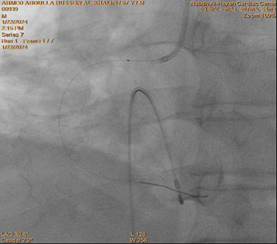

Control angiography of the RCA after thrombus aspiration demonstrated TIMI I

flow. Subsequently, a 1.25 × 10 mm Sprinter balloon (Medtronic Inc.) was

advanced over the guidewire for balloon predilatation. Upon reaching the

proximal RCA, three radiopaque markers were visualized instead of the expected

two (Figure 4). This immediately raised suspicion of device fracture.

Careful inspection of the Export catheter, which had just been withdrawn from

the guiding catheter and was lying on the table, confirmed loss of its distal

tip. This represented a precarious situation, with a thrombogenic broken

catheter fragment retained within a thrombus-laden coronary artery and loss of

operator control over the fragment.